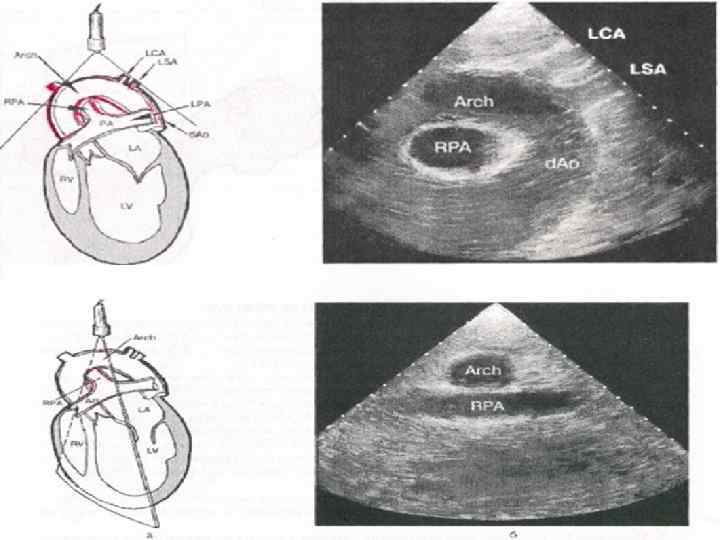

Ультразвуковая анатомия сердца В эхокардиографии используют ряд доступов к сердцу и магистральным сосудам: • Левый парастернальный • Апикальный • Субкостальный • Супрастернальный • Правый парастернальный